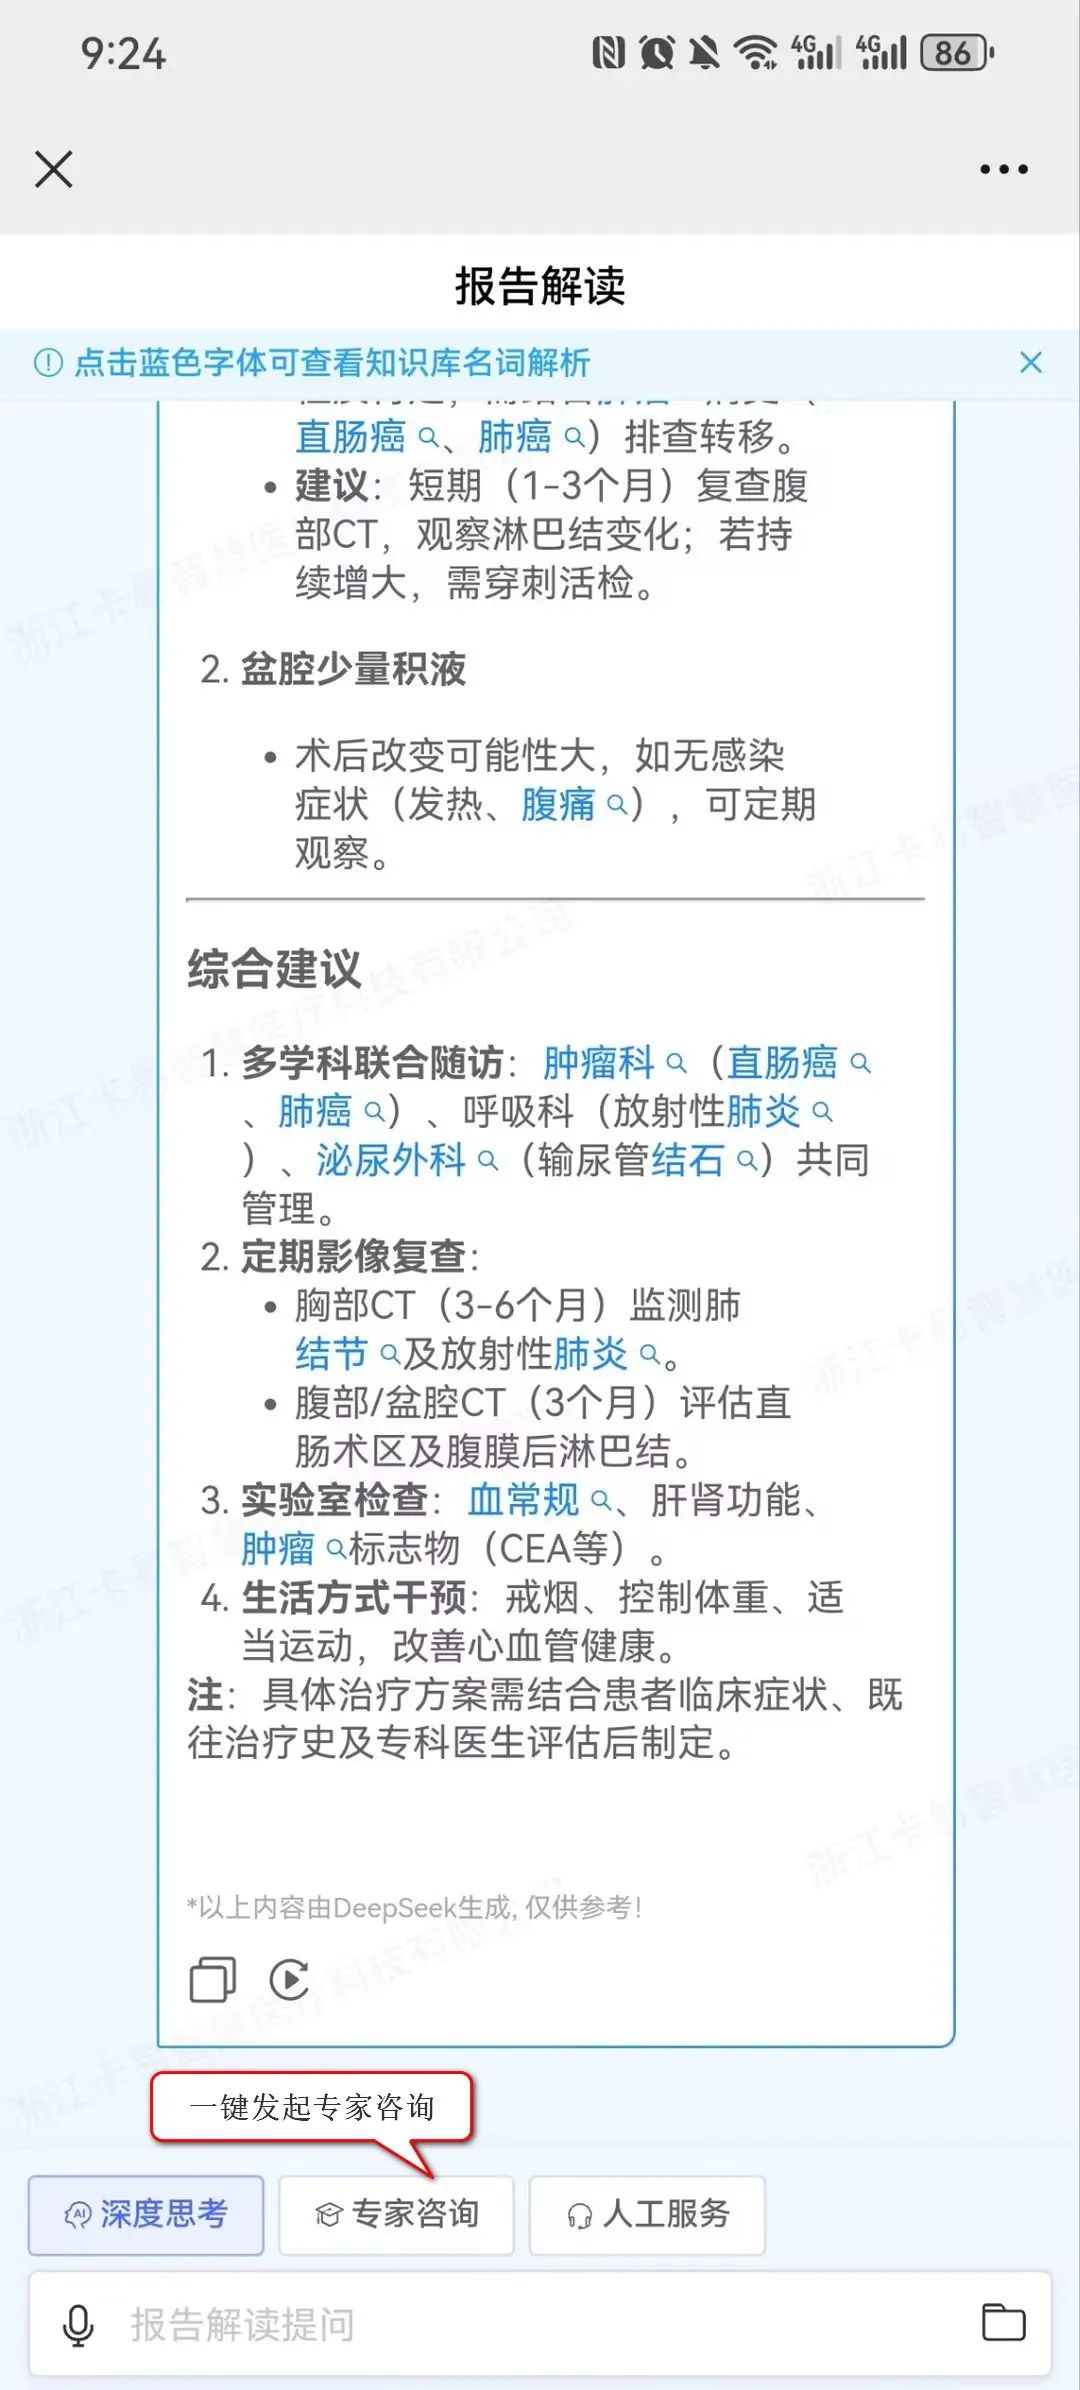

名词解析:点击蓝色字体可查看知识库名词解析,有助于患者更好地理解自己的病情、治疗方案以及预防措施,从而做出明智的健康决策。根据患者的病情和检查结果,推送相关的健康教育内容,例如疾病知识、预防措施、治疗方案等。

影像咨询:当患者对查看的影像或报告内容存在疑问时,可在报告界面直接发起影像咨询,借助DeepSeek获取关于检查流程、报告解读、病情咨询等方面的便捷、专业、优质且经济的建议与服务。若仍有不解,患者还可一键点击专家咨询,迅速发起线上问诊,由平台专家提供权威解答,这一流程不仅极大地优化了患者的就医体验,也显著提升了医疗服务的效率与质量。